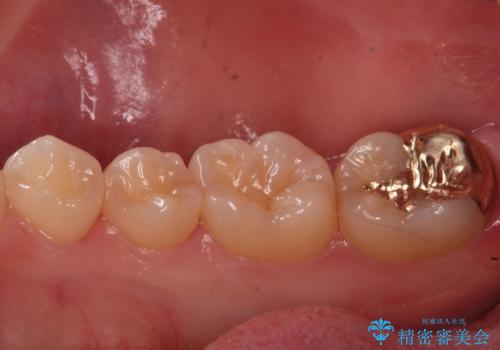

虫歯治療後、精度の良いゴールドアンレーへ

- 検査の結果虫歯が見つかった患者様です。

親知らずを抜歯してから虫歯を除去した後、ゴールドの詰め物で修復します。

比較的大きな虫歯でしたがゴールドでの修復にすることで歯の削る量を抑え、精度の高い治療を行うことができました。

親知らずの問題も同時に解決することで今後の虫歯リスクを抑えています。